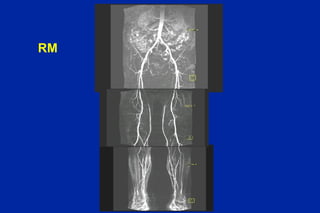

Este documento resume los principales tipos y técnicas de angiografía. Describe brevemente la angiografía, arteriografía, flebografía y linfografía, así como las técnicas de contraste y materiales utilizados. También explica los principales accesos vasculares, la técnica de Seldinger, la angiografía por sustracción digital y algunas técnicas endovasculares comunes.